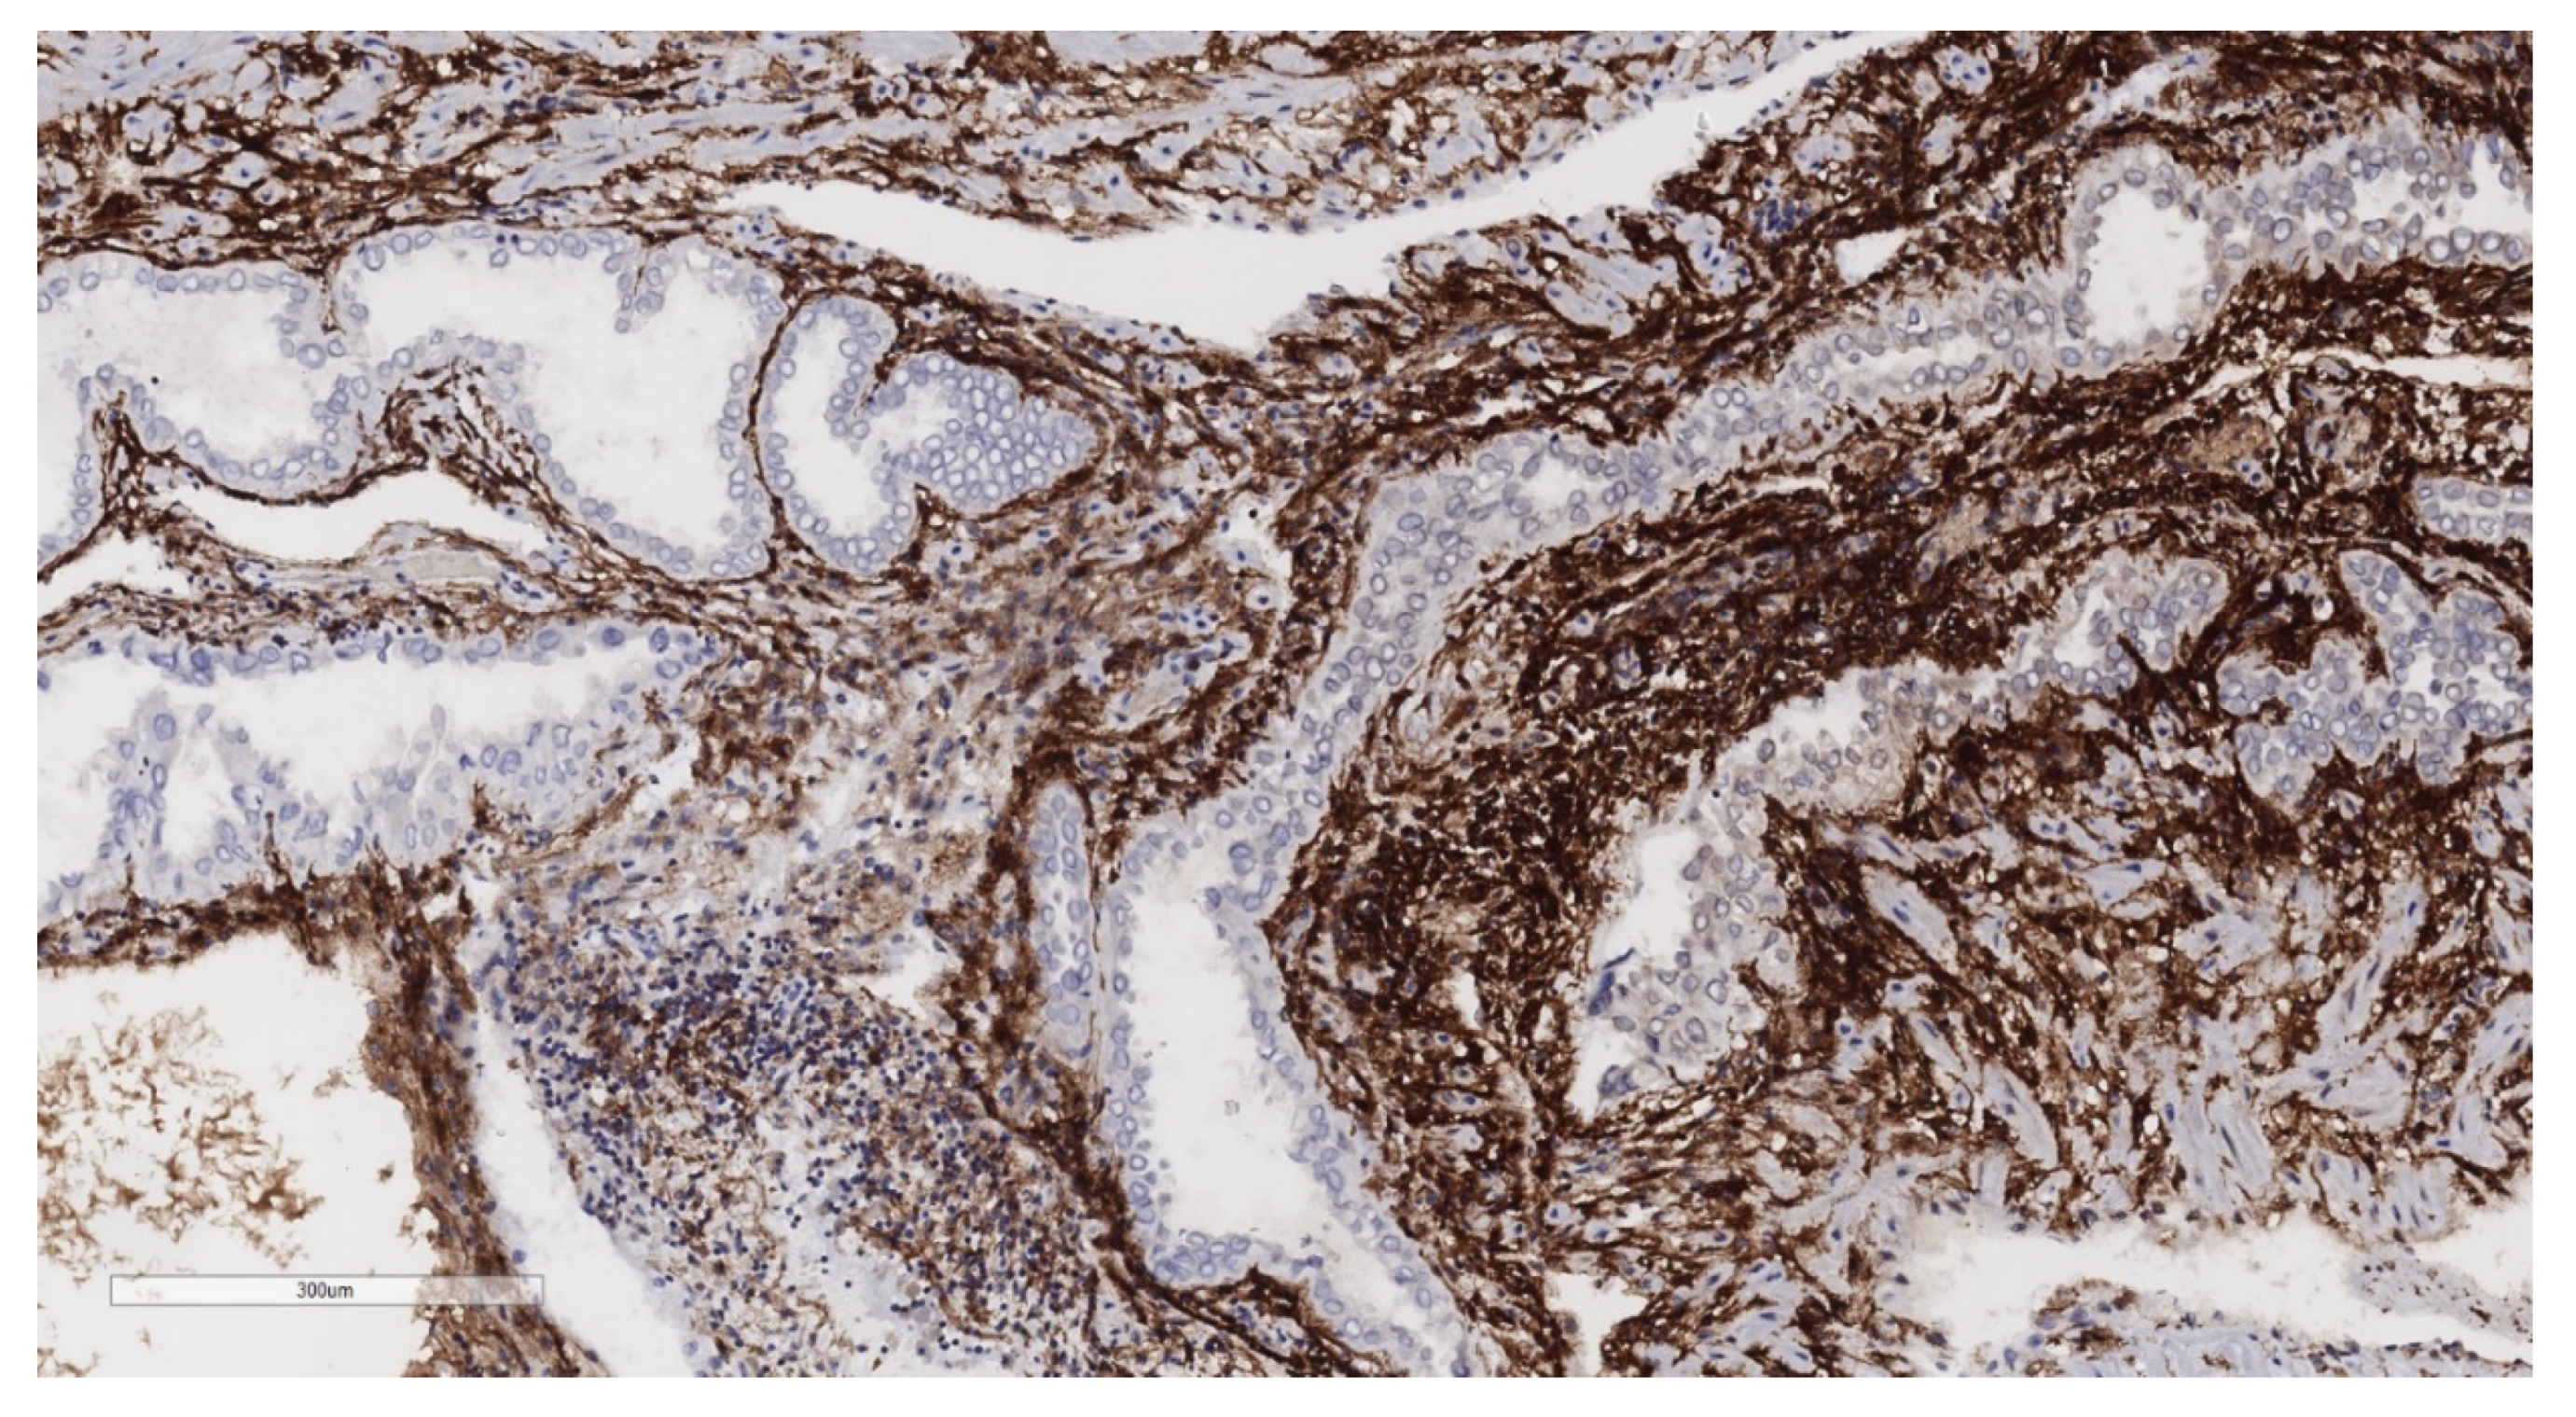

2.2. Histopathological Analysis